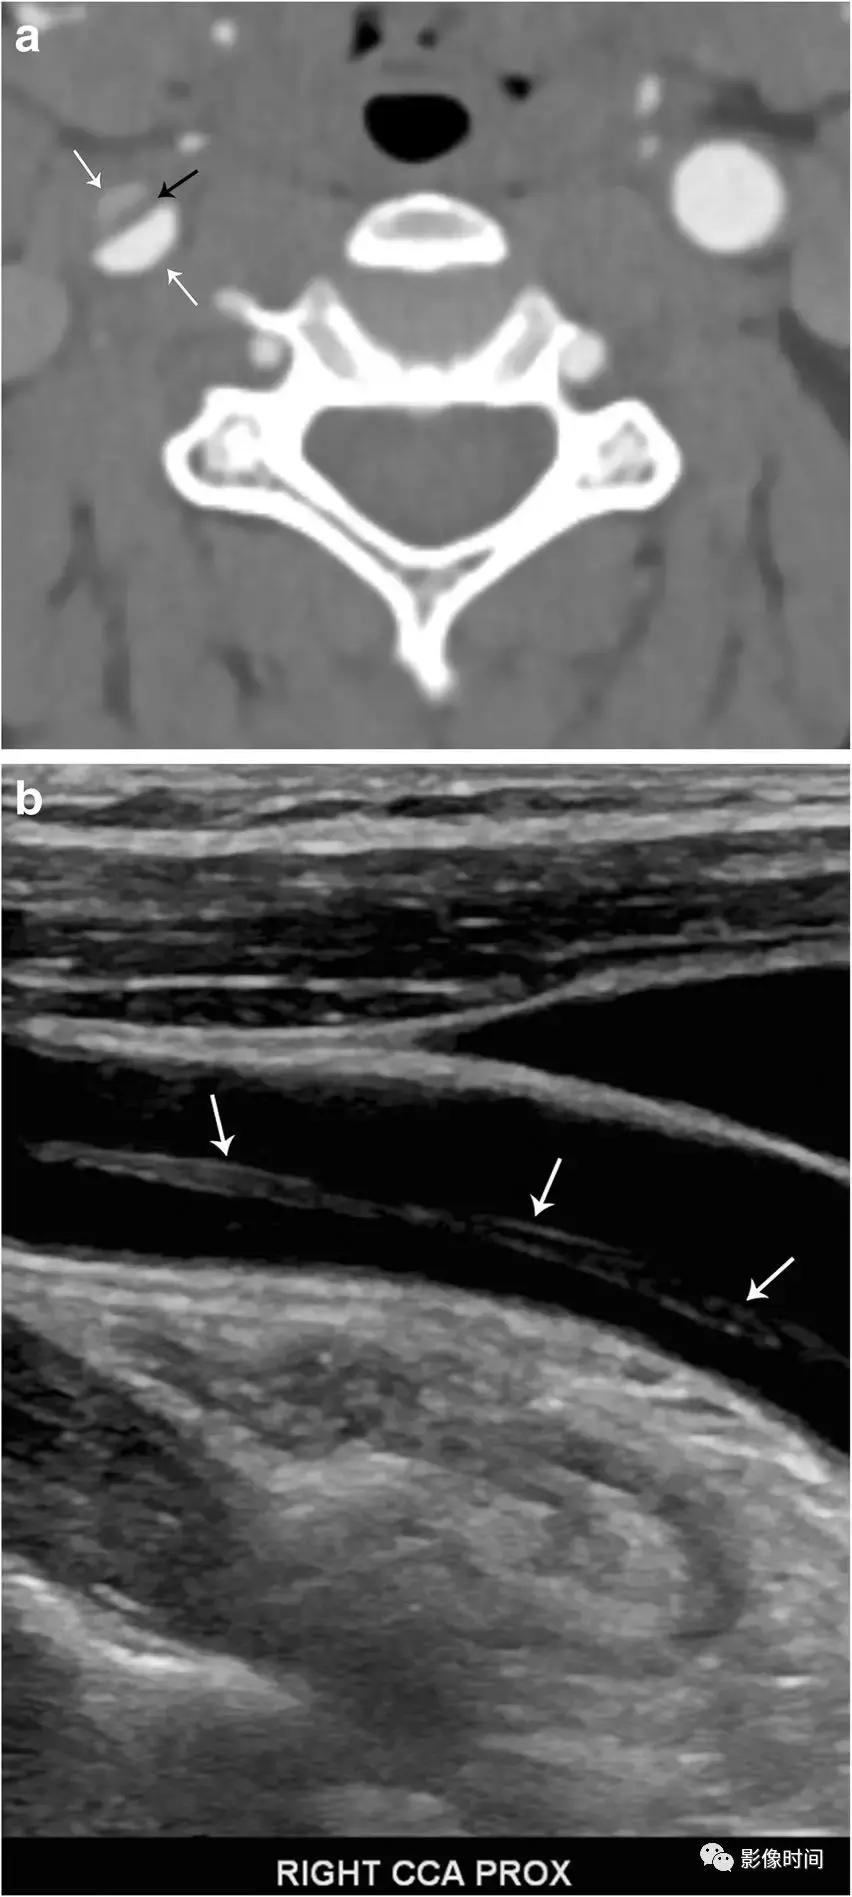

模式图显示了颈内动脉夹层,内膜撕裂,血肿位于中膜,真腔狭窄。DSA 显示真腔狭窄 (黑色箭头)。轴位 CTA、超声下显示右颈总动脉有内膜瓣 (黑色箭头) 和「双腔」征 (白色箭头)。轴位 T1WI-压脂显示右侧颈内动脉高信号新月形壁间血肿,真腔明显狭窄,右侧颈内动脉显示正常流空信号。